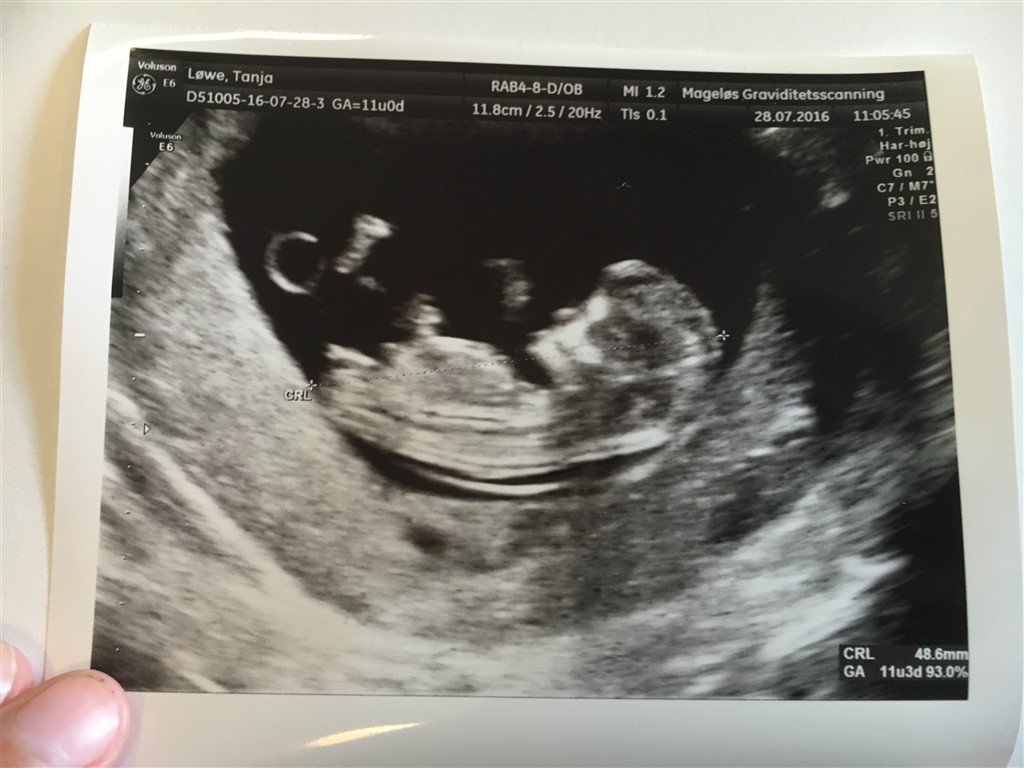

Hvad er nub teorien? Og hvad ser i udfra den ?

nub teori��?

Hvis du ser mit scanningsbillede fra forleden kan du ved "numsen" se en lille "tap" og hvis den går lige ud eller ned af ift. Rygsøjlen så er det en pige og hvis den går op ad (mener over 30*) er det en dreng

har svært ved at se det udfra dit, men er også total nybegynder - fandt først ud af hvad  nub teorien var i torsdags

Nårh ja så kan man jo faktisk slet ik vudere ud fra mit scannings billed når man ik ka se det stykke . Må vente til lidt og bestille en køns scanning ������